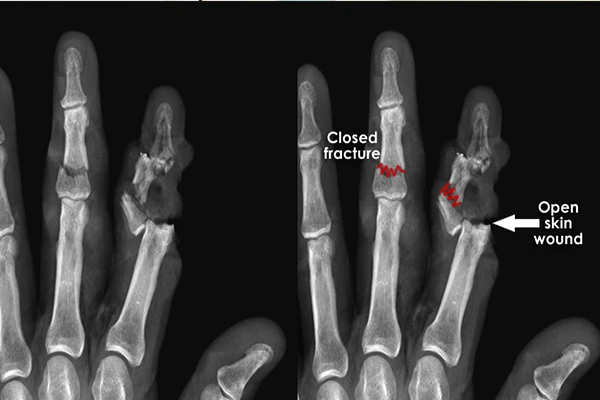

Patient Positioning in Radiography: A Visual Guide

A guide to positioning for common projections like chest, hand, and foot X-rays.